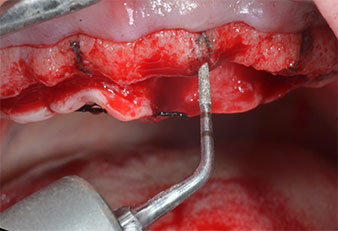

Posizioni dell'impianto

Fig. 2: dopo l'incisione crestale sulla linea mediana e la preparazione dei lembi mucoperiostei, le posizioni dell'impianto vengono trasferite all'osso.

Uno strumento piezoelettrico (Piezomed I1) a forma di fiamma, rivestito in diamante, è stato usato per contrassegnare le posizioni dell'impianto e per eseguire una preparazione pilota (Fig. 3). Si è prestato attenzione a utilizzare un movimento verticale ascendente e discendente, con potenza ridotta, irrigazione completa e bassa pressione (inferiore a 300 g). Successivamente è stato applicato uno strumento pilota (Piezomed I2A/I2P) per l'ingrandimento iniziale delle sedi dell'impianto del diametro di 2 mm (Fig. 4), seguito da un inserto da 3 mm (Fig. 5).

Strumento marcatore a ultrasuoni Piezomed

Fig. 3: la preparazione con lo strumento marcatore a ultrasuoni Piezomed I1 viene eseguita in un movimento verticale ascendente e discendente, parallelo all'asse longitudinale della parte lavorante.